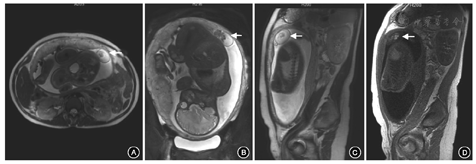

患者30岁,孕2产1,末次月经2017年7月8日。2018年4月16日,患者因"停经40周+2,阴道分泌物增多半天"入院。患者于孕11周在本院因"夫妻双方地中海贫血基因携带(女方:--SEA/αα,β-28/βN;男方:αα/αα,βIVS-2-654/βN)"行绒毛活检术,绒毛快速基因检测提示21、18、13号染色体数目均未见异常,绒毛地中海贫血基因检测提示β地中海贫血-28突变杂合子。中孕期排畸超声未发现明显异常;孕33周+超声发现胎盘胎儿面内异常回声,大小为6.9 cm×3.1 cm,以无回声为主,其内可见强回声光团;彩色多普勒血流显像未探及明显血流信号,不排除胎盘畸胎瘤可能(图1)。孕35周+盆腔MRI提示子宫底部左侧、胎盘左上缘偏内侧可见囊性不规则混杂信号影,病灶大小约4.5 cm×3.9 cm×2.7 cm,边缘清晰,边缘可见包膜,考虑畸胎瘤可能,也不排除死胎可能(图2)。2018年4月18日(孕40周+4)经阴道分娩一活女婴,出生体重3 320 g,外观未见畸形,1、5和10 min Apgar评分均为10分。胎盘于胎儿自然娩出后5 min自然完整娩出。病理检查:胎盘大小为21 cm×18 cm×2 cm,胎儿面光滑,母体面完整;在胎盘边缘的羊膜和绒毛膜之间发现1个6.5 cm×5.0 cm×3.0 cm的光滑椭圆形被覆皮肤的结节,质地中等,无蒂(图3)。剖开后切面局部可见软骨。显微镜检查可见完整皮肤结构,有表皮、真皮、皮肤附属物、脂肪组织、肌肉、软骨、骨、血管及神经组织(图4),病理诊断:(胎盘边缘)成熟型囊性畸胎瘤。患者于产后2 d出院。出院后随访1年,患者及其女一般情况良好。

胎盘畸胎瘤的产前诊断主要依靠超声[3]。据国内外文献报道,胎盘畸胎瘤多为单发,胎盘体积明显大于正常胎盘,外形多为光滑的圆形或椭圆形;肿瘤多位于胎盘的胎儿面羊膜和绒毛膜之间,与胎盘之间多通过一短蒂相连;羊膜腔内表现为团块状强回声,内部多无强血流信号。典型的畸胎瘤超声声像图特征可以表现为脂液分层征、面团征、瀑布征、垂柳征、壁立结节征、多囊征、杂乱结构征、线条征及星花征等[9]。但是超声存在一定的局限性。例如,超声的视野有限,穿透性容易受影响,且超声评估可能受到胎儿位置、孕妇肥胖、羊水过少等限制,故必要时可以考虑进行MRI检查。本例在中晚孕期超声中发现胎盘的胎儿面羊膜和绒毛膜之间存在一囊性椭圆形异常回声,并进一步行MRI辅助诊断。超声对瘤体内血管、钙化、囊性成分较敏感,而MRI对瘤体内各软组织成分组成较敏感,两者联合应用,可以较好地明确瘤体性质。另外,联合应用血清生物学标志物(如癌胚抗原、甲胎蛋白、绒毛膜促性腺激素等),能够检测体积>17 mm3的畸胎瘤,灵敏度>87%[16]。组织病理学是确诊的手段。在检索到的个案报道中,显微镜下多可发现成熟脂肪组织,往往也含有皮肤、皮肤附属物、骨、软骨、肌肉、神经组织或肠上皮细胞等。本例镜下可发现一些来自中胚层和外胚层的组织,但并未发现来自内胚层的肠腔上皮或消化腺上皮组织。这进一步说明畸胎瘤是一种来源于具有多向分化潜能的生殖细胞的肿瘤,可分化为一个或多个胚层组织。